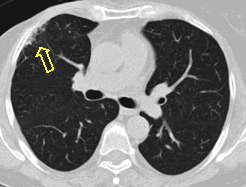

21. Left sided peripheral lung tumor

22. Central lung tumor with mediastinal lymphadenopathy. CT coronal and sagittal reconstructions.

70 year old man, COPD, hoarse. Right hilar mass, bronchoscopy was negative.

The larynx is rotated to the right, no motion of the right side of the larynx can be observed, swollen left plica ventricularis area.

CT: 13x11 mm large nodular mass in the left 10th segment. Bilateral hilar lymphadenomegaly with central hypodensity. A 34x21 mm large lymph node conglomeration can be observed in subcarinal location (peripheral contrast enhancement). Lymphadenopathy in the aortopulmonary window (15 mm large), and a 26 mm large lymph node can be observed in paraaortic location above the trachea bifurcation which has an esophagus-compressing effect. In the superior chest aperture there is a 38x28 large fused lymph node conglomerate which causes the left shift of the esophagus and trachea.